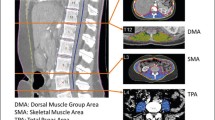

We included 107 healthy Caucasian patients (46 males; 61 females) with a healthy BMI (18–25 kg/m2) for analysis. Body composition data were obtained from a single transverse CT image at the mid-third lumbar vertebrae using ImageJ software. Tissue segmentation was performed using Hounsfield unit thresholds of −29 to +150 for muscle and −190 to −30 for adipose tissue.

CT scans were assessed for quality as previously described [16]. Data were obtained from a transverse CT image at the mid-third lumbar vertebrae using ImageJ software (National Institute of Health, Bethesda, MD, USA). Tissue segmentation was performed using Hounsfield unit thresholds of −29 to +150 for muscle and −190 to −30 for adipose tissue [16, 17]. The cross-sectional area of subcutaneous adipose tissue (SAT), VAT and muscle were measured and normalized for stature (cm2/m2), and described as subcutaneous adipose tissue index, visceral adipose tissue index and SMI as previously reported [18]. Patients were divided into sex- and age-specific groups since these two variables are known to have significant impact on body composition variables. Twenty subjects had a CT with only partial SAT area and were classified as missing data for analysis.